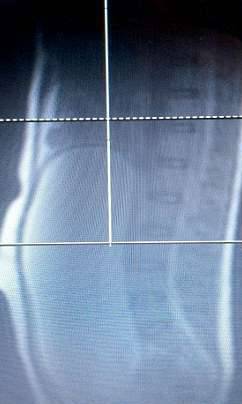

▼直到最近肚子疼痛难忍,她才到医院检查。医生以为奥莉薇亚要分娩,扫描后才发现她的卵巢中长了一个30公分左右的大囊肿。这个恶性囊肿重达9.5公斤,可能引发癌变。

▼医生发现她的卵巢中长了一个大囊肿。